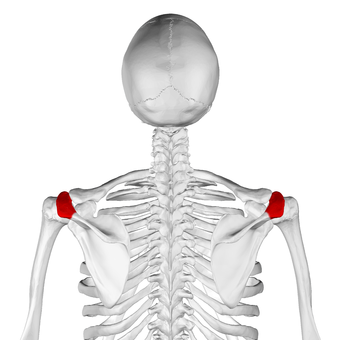

الأخرم (من اليونانية: أكروس، "الأعلى" ōmos، "الكتف"، المفرد: acromia)، هو نتوء عظمي على عظمة الكتف (لوحة الكتف). يمتد الأخرم والناتئ الغرابى جانبياً معاً فوق المفصل الحقاني العضدي. يتمفصل الأخرم مع الترقوة ليكوّنا المفصل الأخرمي الترقوي.

البنية

الأخرم يشكل قمة الكتف، وهو نتوء كبير، شكله مثلث إلى حد ما أو مستطيل، مفلطح من الخلف إلى الأمام، يبرز أوله وحشياُ، ثم يتقوس إلى الأمام و إلى الأعلى، ثم يتعلق مشرفا على التجويف الحقاني.[1]